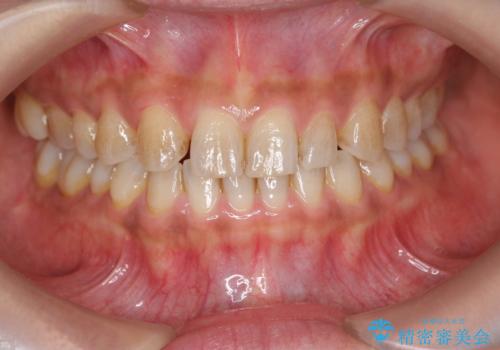

前歯のがたつき 過蓋咬合